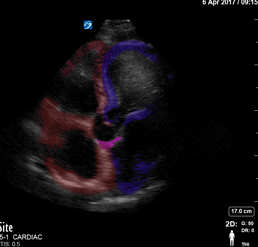

Colorized Atlas - Apical 4 - Colorized Simple

Apical 4 Red: Right atrium and ventricle, Blue: Left atrium and ventricle, Pink: aortic valve Images: Dr. Lindsay Davis, Dr. Hannah Kopinski. Image Editing: Michael Amador and Dr. Matthew Riscinti